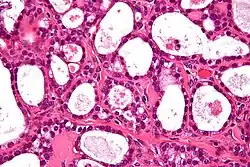

Ovarian clear-cell carcinoma often occurs as a pelvic mass that rarely appears bilaterally. The cells usually contain glycogen with large clear cytoplasm. It is also associated with endometriosis, a disorder of abnormal tissue growth outside of the uterus.[3] The tumor cells emerge in a stepwise manner from adenofibromas which are benign endometriotic cysts. They also hold molecular genetic mutations in both ARID1A and PIK3CA, similar to other epithelial ovarian cancers. Mutations in ARID1A commonly contain phosphatase and tensin homolog (PTEN) that are hypothesized to contribute to clear-cell tumorigenesis. However, research also shows that inactivation of ARID1A alone does not lead to tumor initiation. However, clear-cell tumors rarely carry p53, BRCA1, or BRCA2 mutations.[4] In addition, they also test negative for estrogen and progesterone receptors and Wilm tumor suppressor 1.[5] Studies have also suggested that clear-cell carcinoma can occur with thromboembolic complications and hypercalcemia. Recurrence of tumor cells have been reported to involve lymph nodes and parenchymal organs.